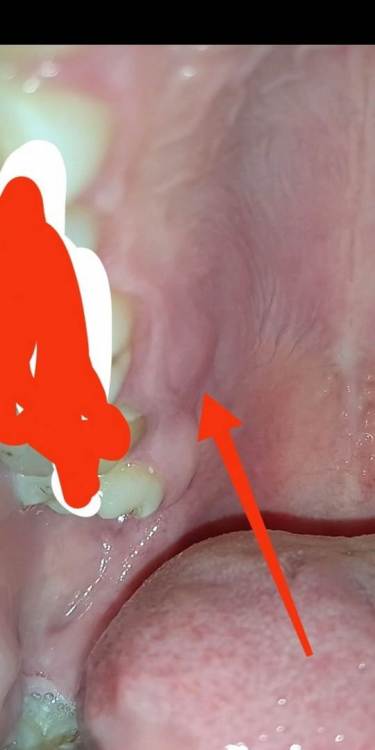

Мариna Опубликовано 9 ноября, 2021 Поделиться Опубликовано 9 ноября, 2021 Здравствуйте, ситуация: болит десна. (фото с интернета, место указано стрелками) зуб мудрости вылез где-то на протяжении 2 недель, на 7 нарощенный зуб+ штифт, думала, что зуб мудрости двигает остальные зубы, но нет, места хватило, он стал нормально, даже зубная нить отлично проходит между зубами. А вот десна болит, при нажатии языком. Спасибо Вам за ответ и труд! Ссылка на комментарий

Женька Опубликовано 9 ноября, 2021 Поделиться Опубликовано 9 ноября, 2021 @Мариna на данном фото из интернета - съёмный зубной протез. Как Вам помочь по фото из интернета хороший вопрос. 1 Ссылка на комментарий

Женька Опубликовано 9 ноября, 2021 Поделиться Опубликовано 9 ноября, 2021 @Мариna с какой целью жевательные поверхности замазали? или опять фото из интернета? Ссылка на комментарий

Мариna Опубликовано 9 ноября, 2021 Автор Поделиться Опубликовано 9 ноября, 2021 Работы с зубами непочатый край... по генетике зубы плохие, с детства не уберегла. может этому поспособствовать восьмерка? Ссылка на комментарий